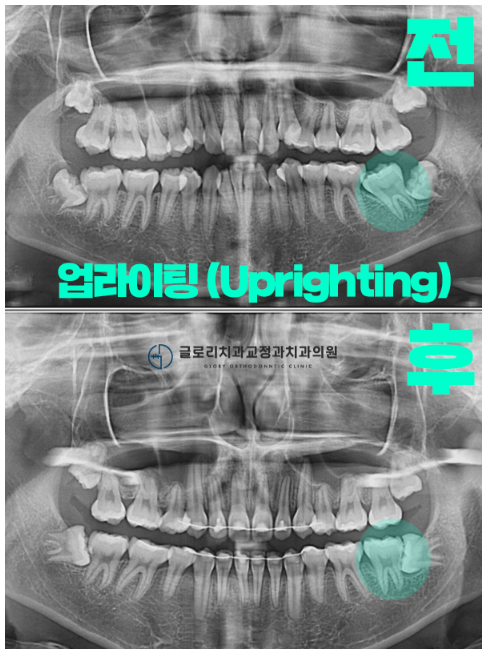

* 업라이팅 (uprighting)

: 누워있는 치아를 세워서 제자리로 위치시키는 것.

주로 미니 스크류를 사용하여 진행

무엇보다 중요한 쓰러진 어금니!

과연 제위치를 찾을 수 있었을까요?

다행히 원하던 대로

알맞게 자리를 잡고 있는 것이 관찰됩니다.

파노라마로 확인을 하면

그 차이가 더 크게 느껴지실 텐데요.

쓰러져 있던 전과는 달리,

올곧은 형태로 맹출 되어 있는 것이 관찰되었습니다.